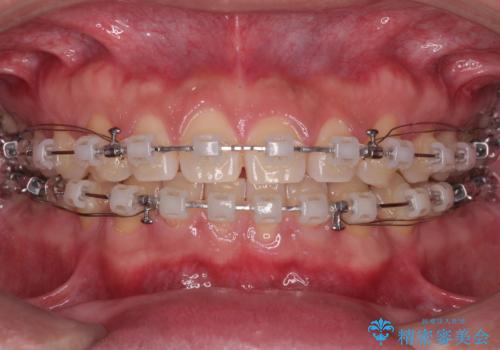

- クリアブラケット

- 1年7ヶ月

舌のトレーニングをしっかりと行ってくださったおかげで、順調に治療を終えることができました。

舌の突出癖が速やかに改善され、後戻りによるスペースは今のところ認められておりません。